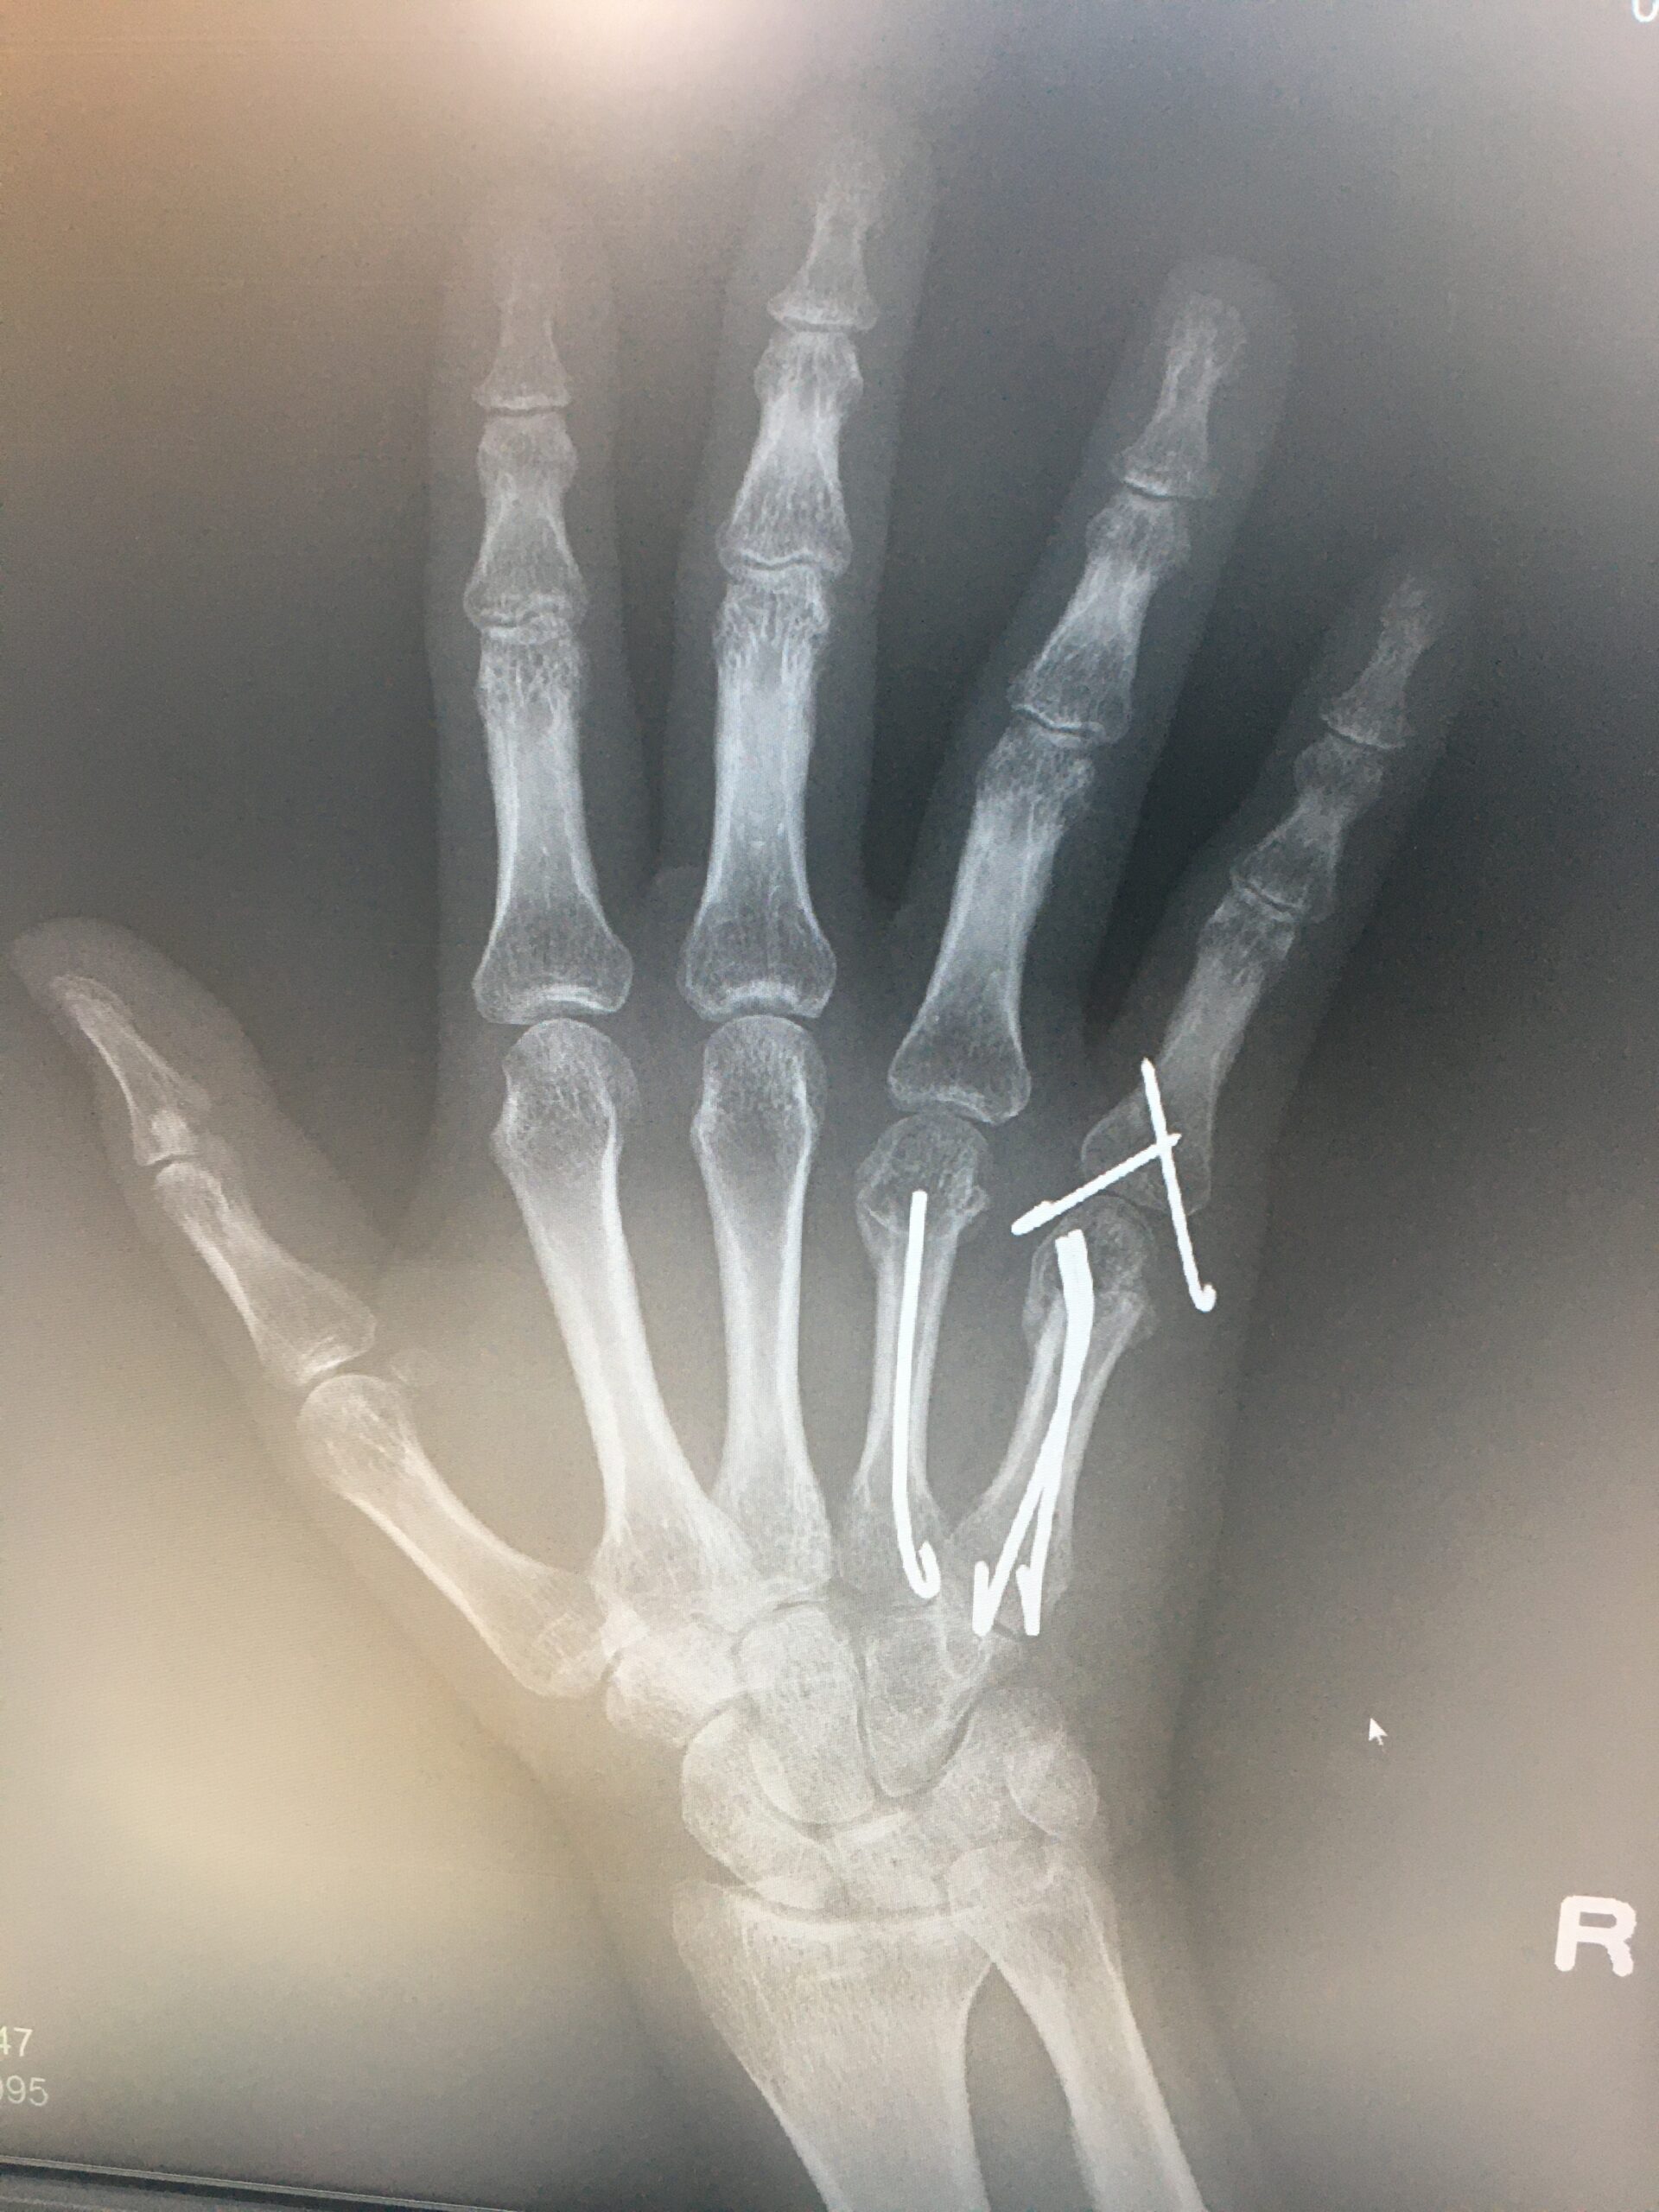

右手薬指及び小指の中手骨骨折する前の演奏動画